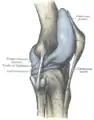

Anterolateral aspect of right knee

Anteromedial aspect of right knee

The ligaments surrounding the knee joint offer stability by limiting movements and, together with the menisci and several bursae, protect the articular capsule.[16]